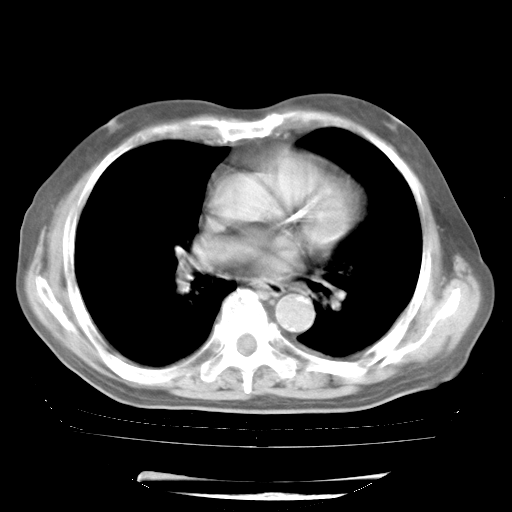

轻微咳嗽,无痰,(体温正常时)R20次/分,P75次/分,双肺底、腋下可闻及少量捻发音。下肢轻度浮肿。

ECG:右心室增大

心脏超声检查:无右心室增大。